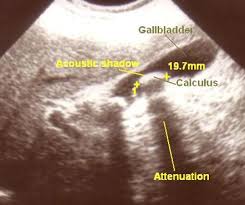

USG Batu Empedu: 5 Fakta yang Wajib Anda Tahu Sebelum Pemeriksaan

Pemeriksaan USG batu empedu sering kali menjadi langkah pertama yang direkomendasikan dokter ketika pasien mengeluhkan nyeri perut di bagian kanan atas. Prosedur ini sangat penting untuk mendeteksi keberadaan, ukuran, dan jumlah batu empedu. Namun, bagi sebagian orang, pemeriksaan ini mungkin menimbulkan rasa cemas atau kebingungan. Artikel ini akan membahas lima fakta penting yang perlu Anda … Read more